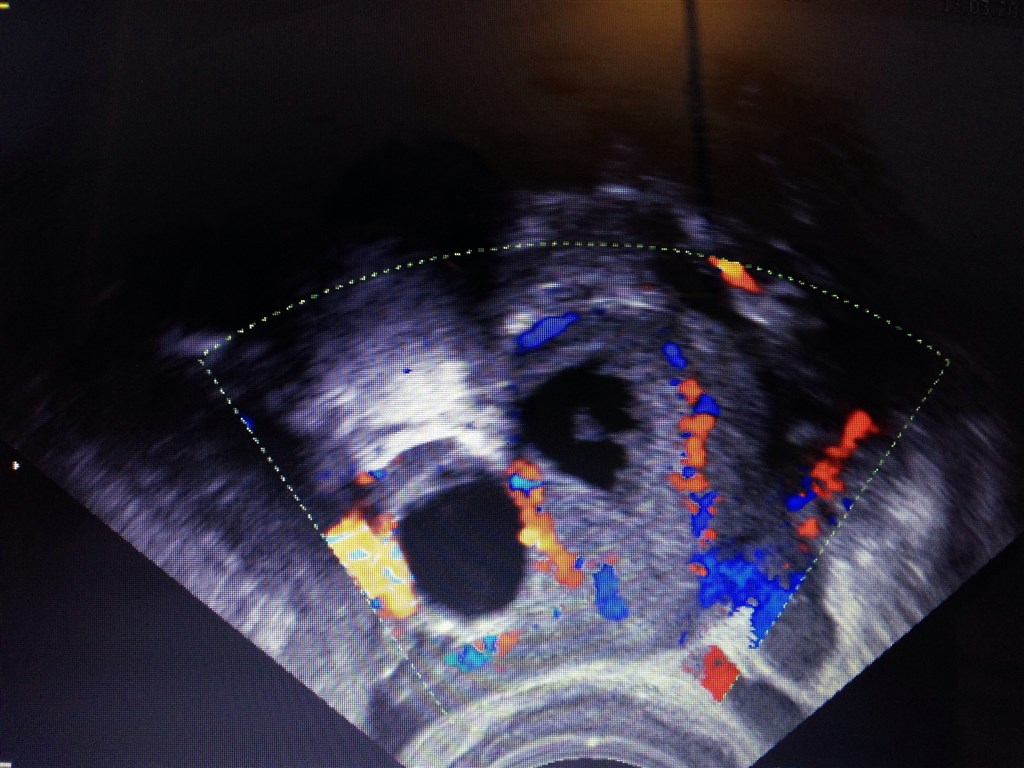

Har efterfølgende set dette billed på dvd jeg fik med hjem..

Vedhæftede fotos (klik for at se i fuld størrelse)

ja altså det sidste billede, ville da tyde på tvillinger